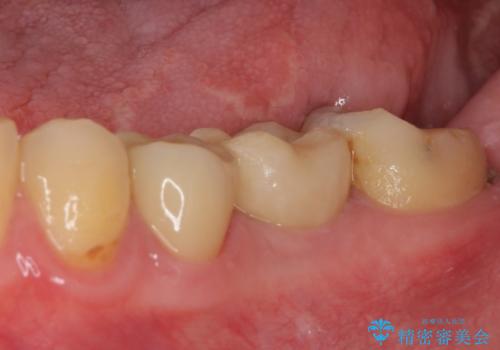

セラミッククラウンによる奥歯のむし歯治療

- 奥歯がしみて痛いとのことで来院された患者様です。

既に複数箇所の修復が行われていたため、オールセラミッククラウンにて補綴をすることとしました。

以前装着した修復物が不適であり、歯肉が腫れていましたが、仮歯を装着したことで腫れは解消されました。

歯の痛みだけでなく、歯肉の腫れも改善され、患者様には大変満足していただきました。